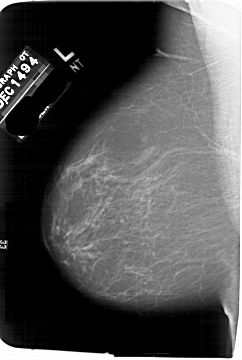

A_1751_1.LEFT_MLO

LEFT_MLO LINES 6826 PIXELS_PER_LINE 4591 BITS_PER_PIXEL 12 RESOLUTION 43.5 NON_OVERLAY